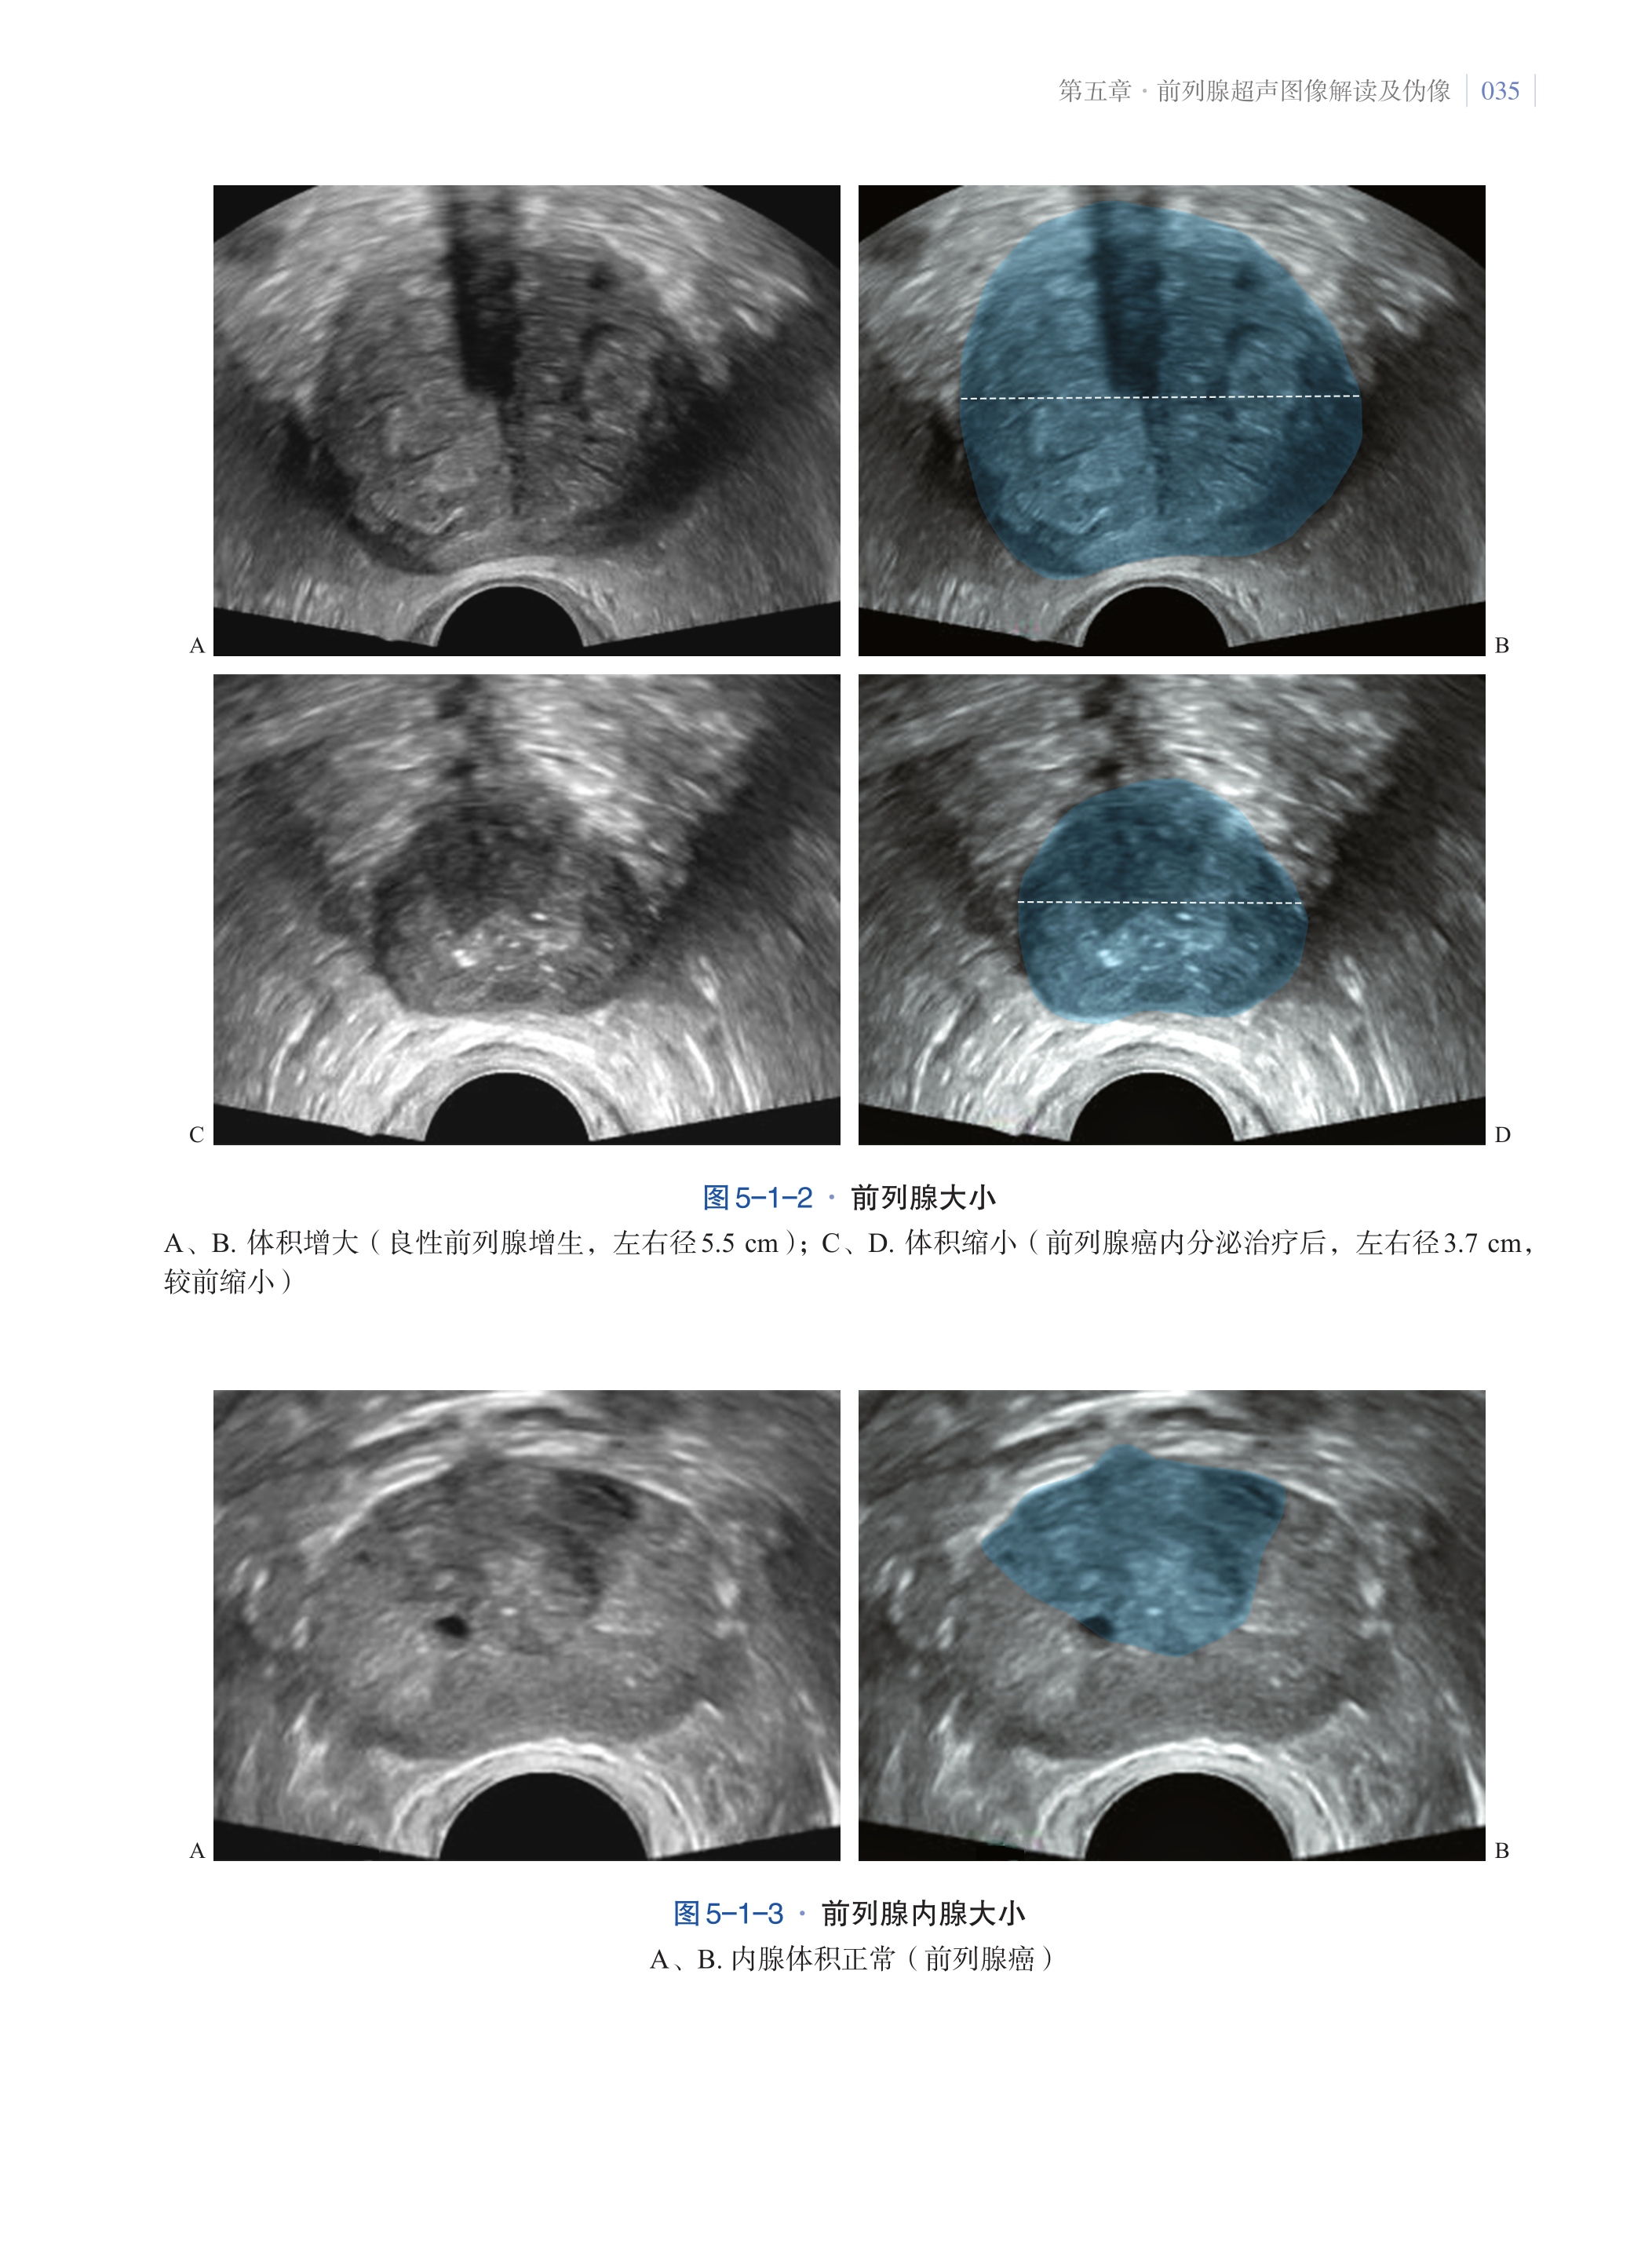

第五章·前列腺超声图像解读及伪像 033

第一节·前列腺超声图像解读 033